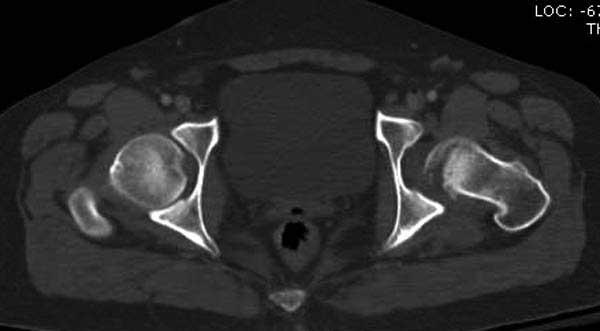

В диагноз еще необходимо внести закрытую (?) ротационно-нестабильную травму таза с переломами лонных седалищных костей, боковой массы крестца справа.

1. Тазовые щипцы, при невозможности (неимении) АВФ на передний отдел таза с попыткой ручной дистракции левого бедра.

2. на правое бедро фиксационный АВФ стержневого типа.

Перелом позвоночника и боковую компрессию таза отнесли к стабильным переломам и не стали форсировать события до лучших времен...

Больная стабильная после хирургических мероприятии и получив добро, приступили к закрытому вправлению таранной кости с укладкой наружного фиксатора. Затем укладка больную на бок и открытый остеосинтез перелома-вывиха головки бедра.